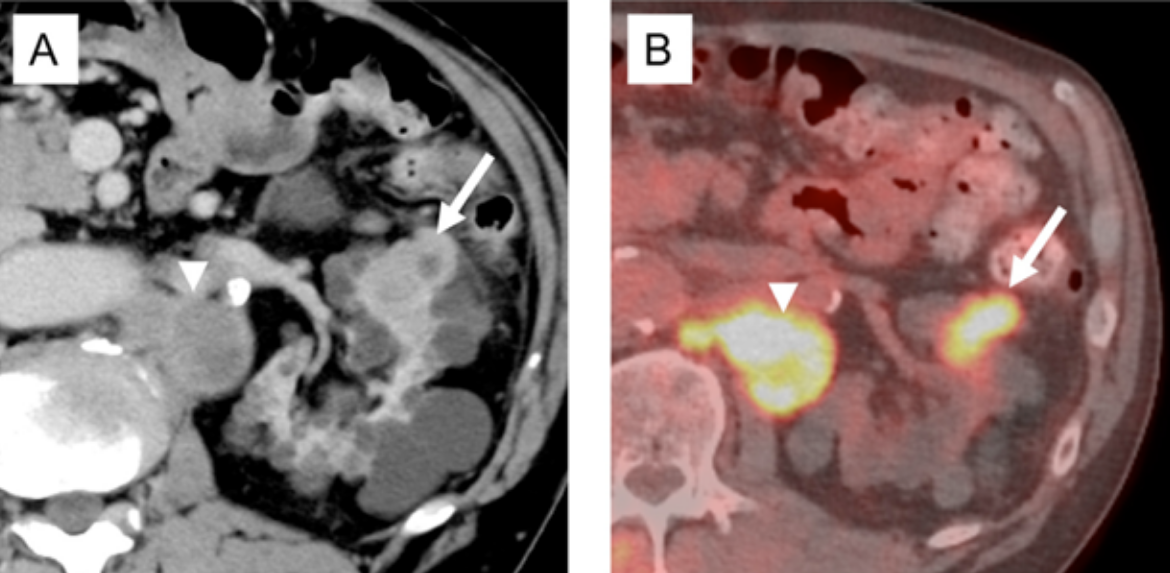

Fumarat hidrataz eksikliği tip renal hücreli karsinom tanılı 64 yaşında erkek hasta.